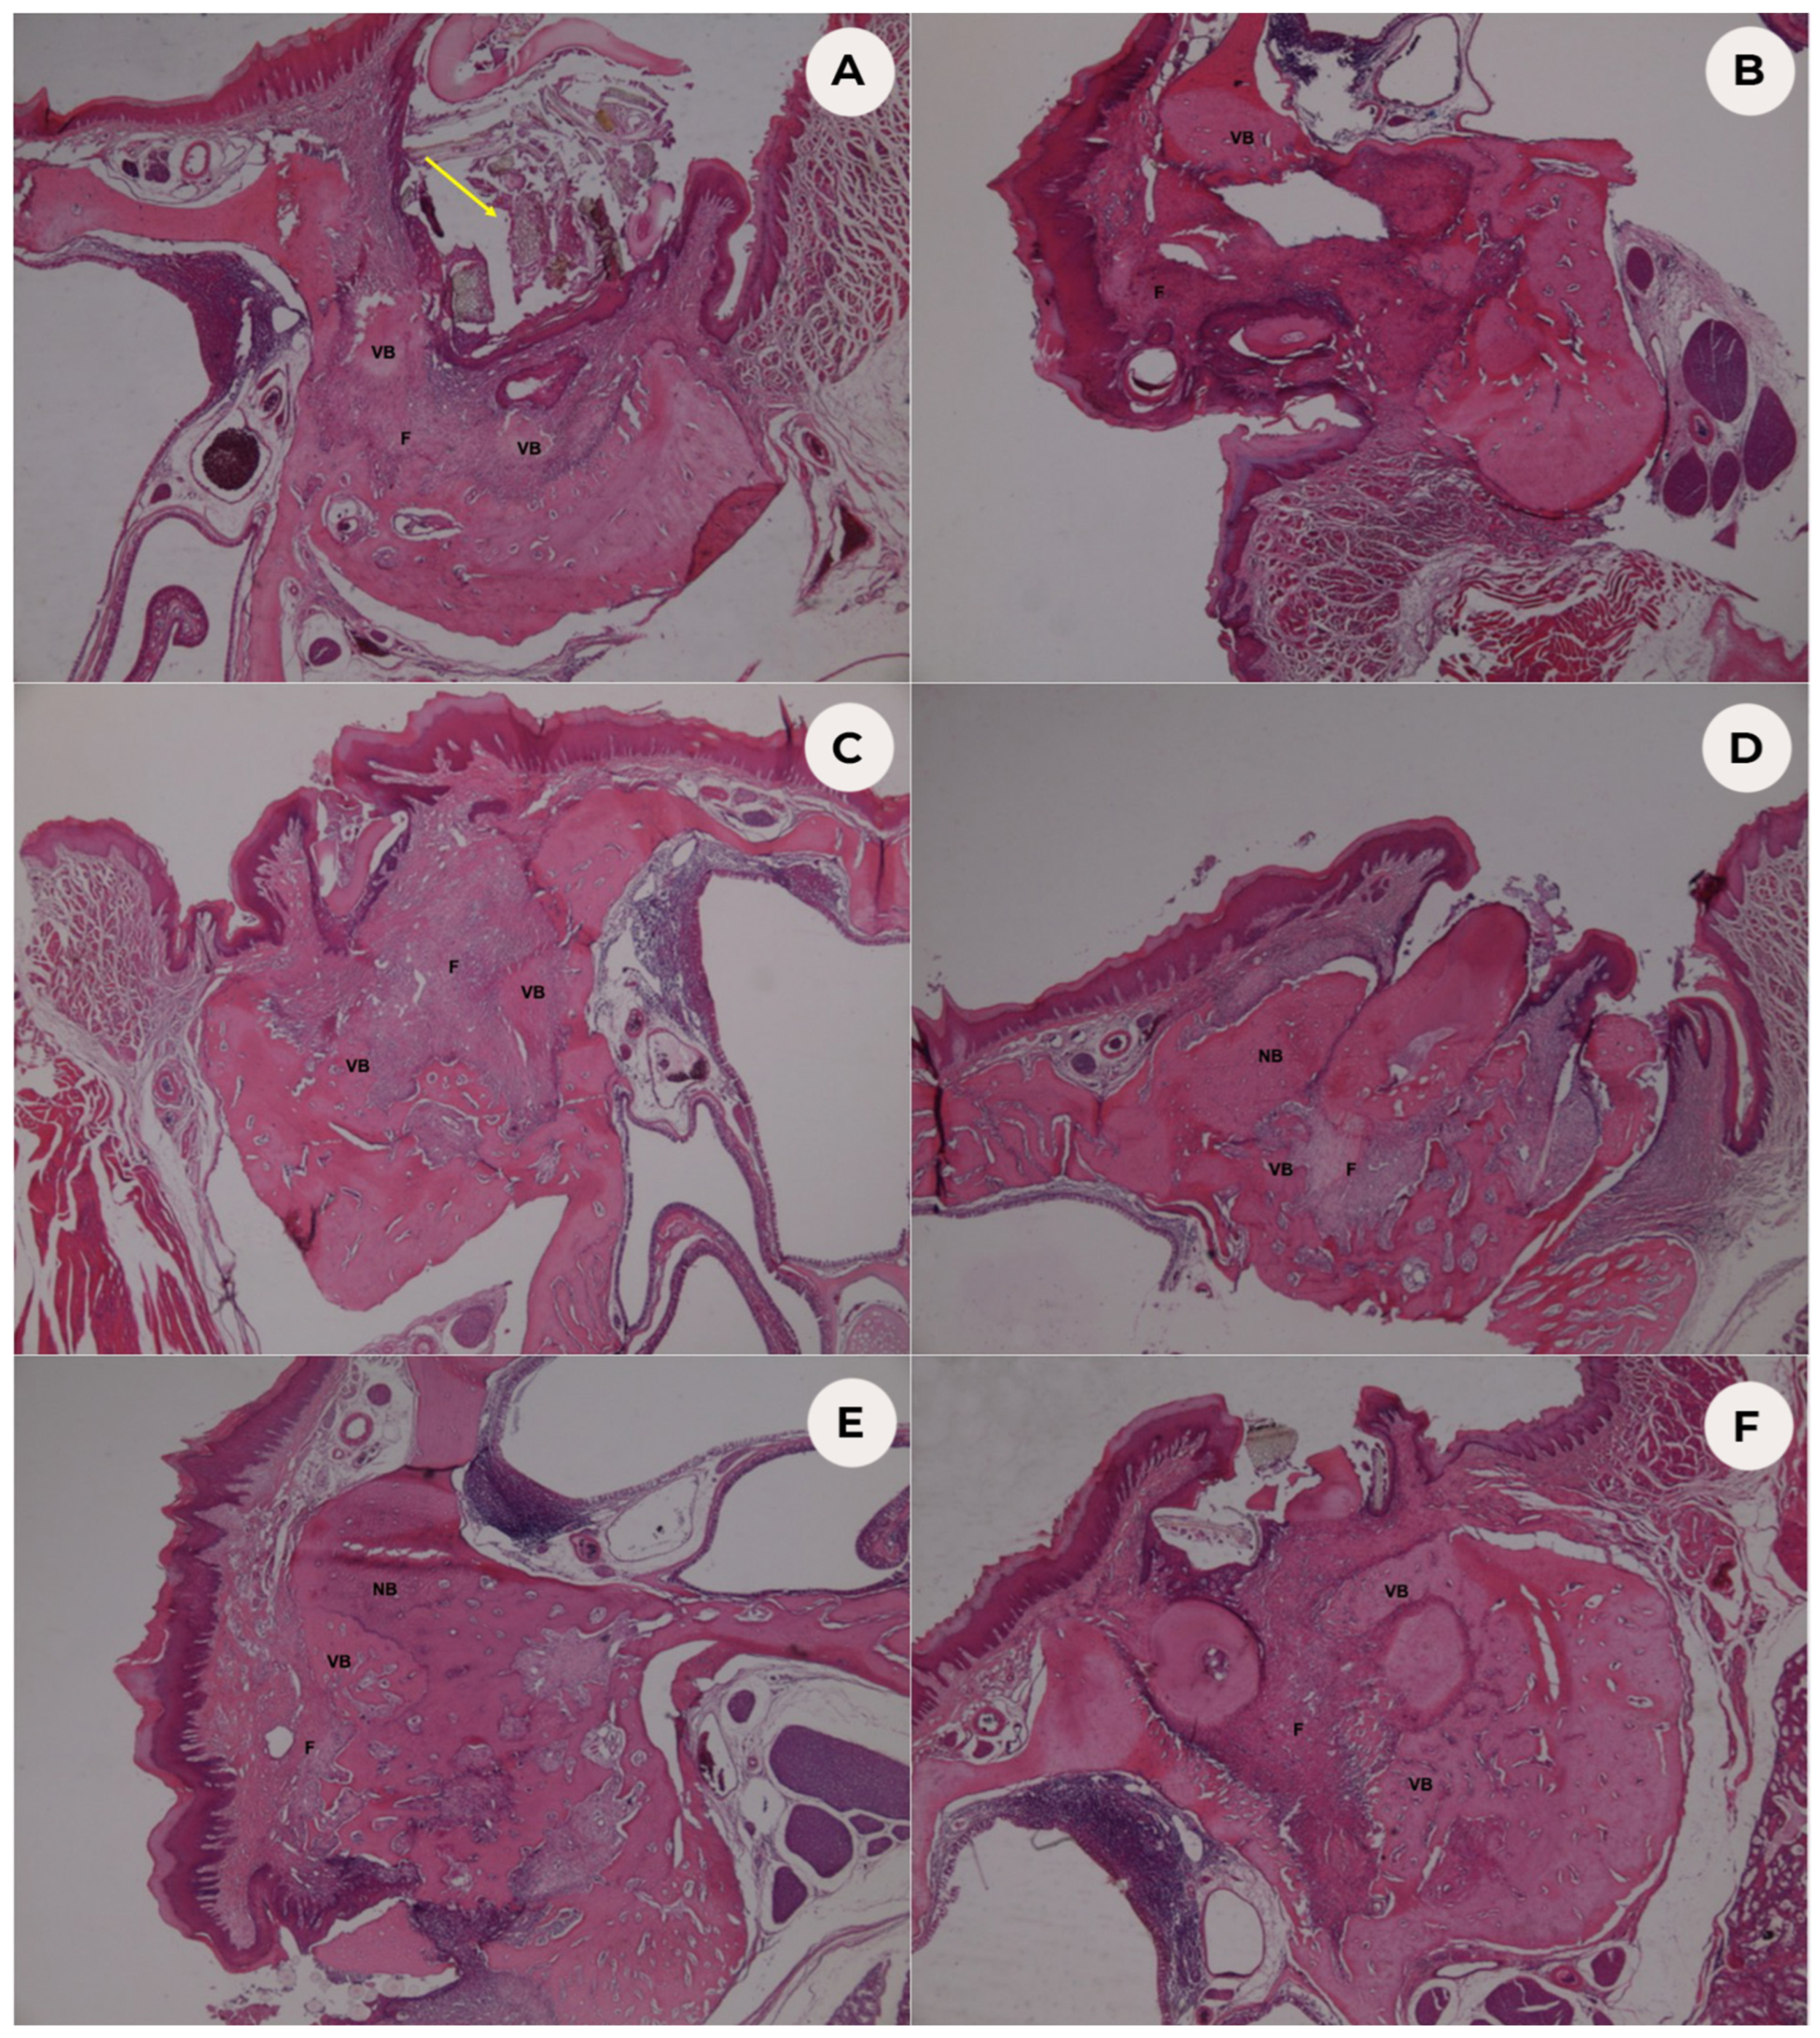

3.1. Histopathological Analysis

3.2. Histomorphometric Analysis